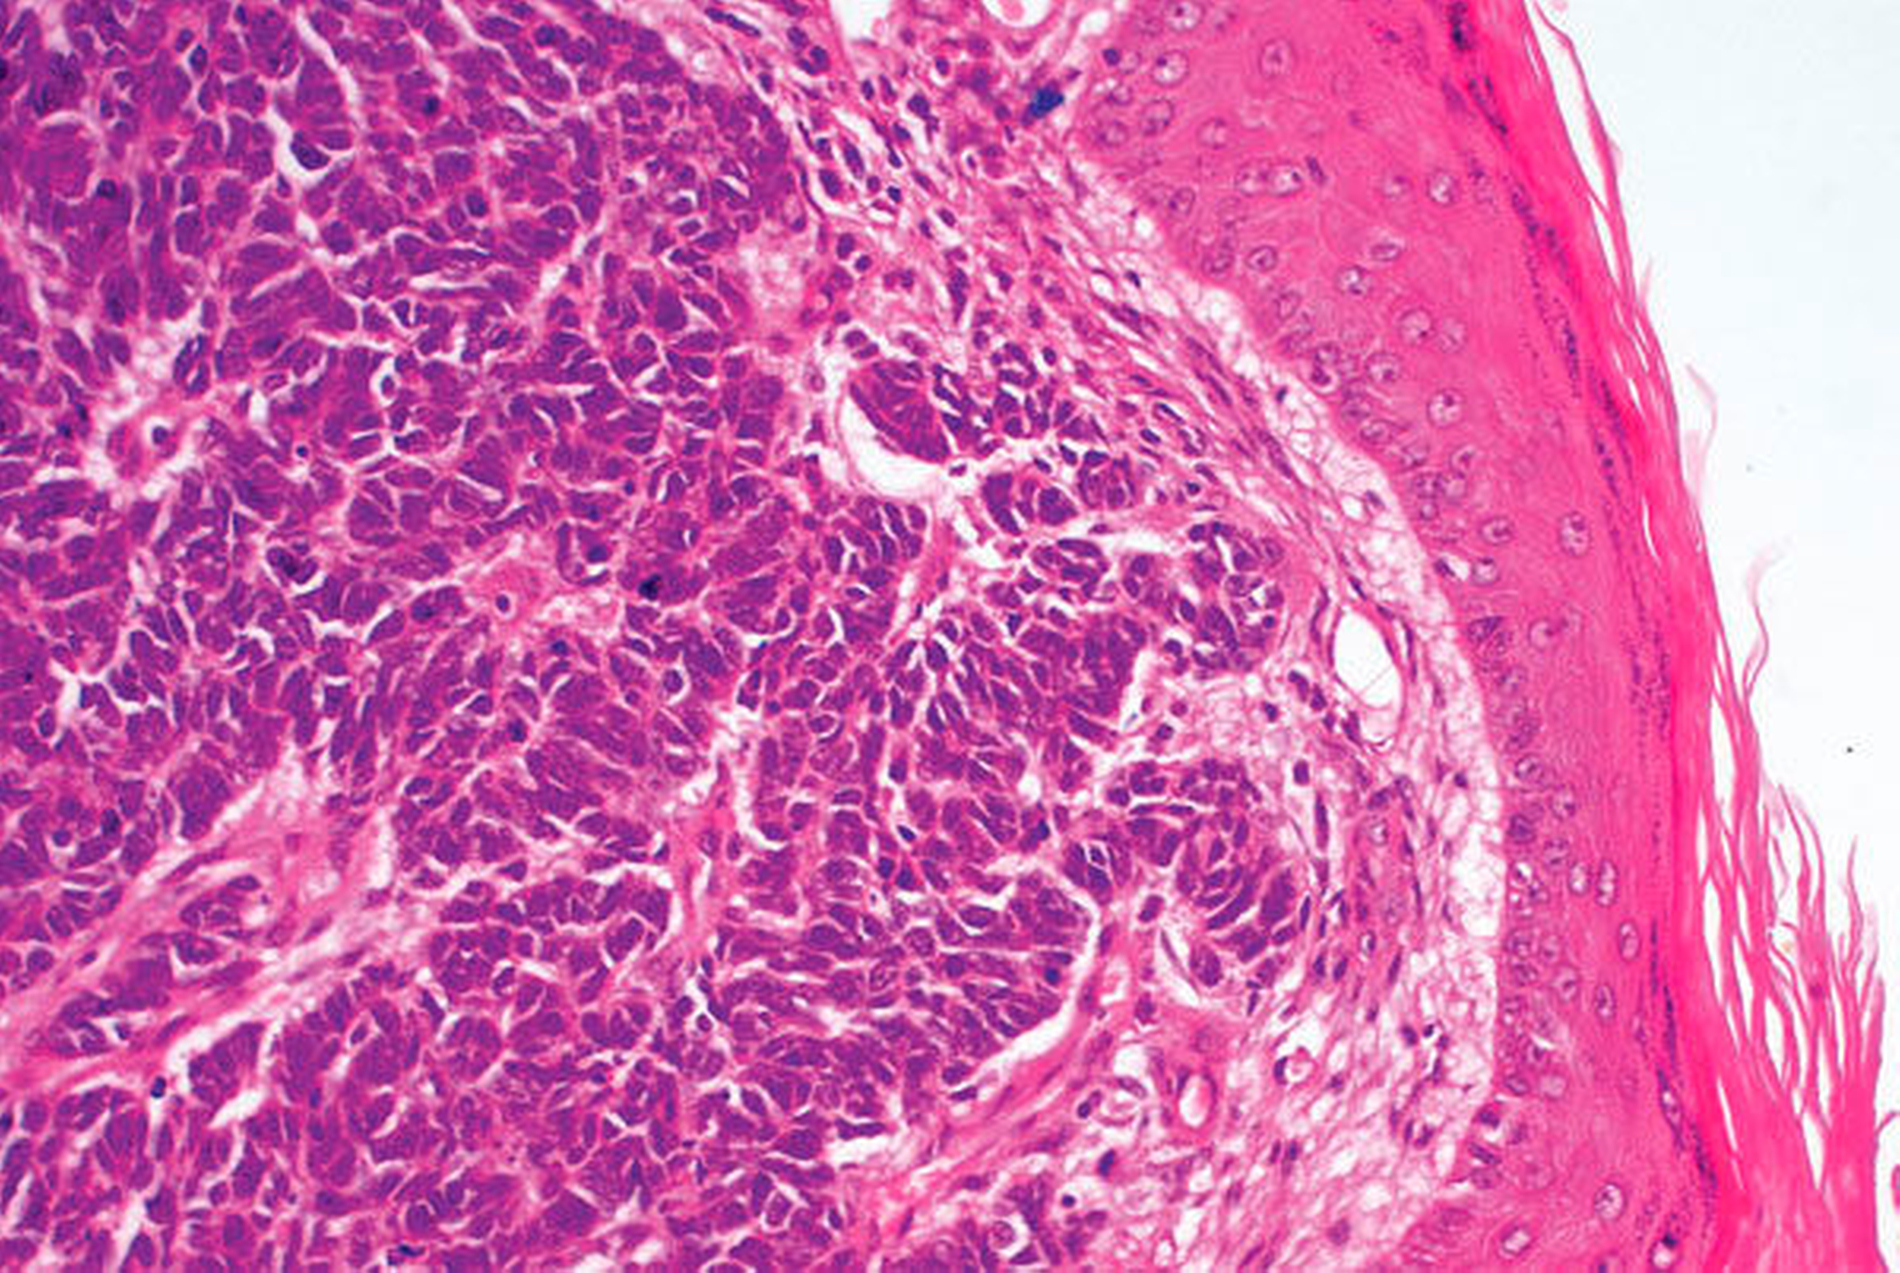

Der Befund zeigte ein R0-reseziertes Merkelzellkarzinom mit multiplen Lymphgefäßeinbrüchen, wobei die tumorfreien Sicherheitsabstände mit 4 mm in horizontaler und 1 mm in basaler Richtung entsprechend der aktuell gültigen S2k-Leitlinie als unzureichend gewertet werden mussten (Abbildung 3). Die beim Merkelzellkarzinom immunhistologisch etablierten Marker CK20 und Synaptophysin waren positiv, der Ki-67-Proliferationsindex lag bei 50 Prozent. Zum Ausschluss einer stattgehabten Lymphknoten- und Fernmetastasierung erfolgte anschließend das weitere Staging mithilfe der sonografischen Halslymphknotenuntersuchung und der Kontrastmittelgestützten CT-Schnittbildgebung der Kopf-Hals-Region sowie von Thorax und Abdomen. Bei klinisch-radiologischer cN0-Situation wurden entsprechend des interdisziplinären Tumorboard-Entscheids die Sentinel-Lymphknotenbiopsie mit Nachexzision des ehemaligen Tumorbetts sowie die plastische Defektdeckung mittels Vollhauttransplantation durchgeführt (Abbildungen 4a bis d). Bei histopathologisch nachgewiesener Lymphknotenmetastasierung erfolgte unter Berücksichtigung des hohen Alters und der umfangreichen Komorbiditäten der Patientin anschließend die isoliert adjuvante Strahlentherapie ohne die beidseitige Ausräumung der Halslymphknoten.

In der HE-Färbung zeigen sich die meist mittelgroßen Zellen klassischerweise monomorph mit hyperchromatisch gelappten Zellkernen und einem schwach gefärbten Zytoplasma. In der Literatur häufig beschrieben wird die histopathologische Ähnlichkeit von MCC mit der des Lymphoms, des kleinzelligen Bronchialkarzinomen, mit Neuroblastomen, Rhabdomyosarkomen und Ewing-Sarkomen, wobei die Abgrenzung zum kleinzelligen Bronchialkarzinom aufgrund seiner Häufigkeit von besonderer Bedeutung ist [Oram, Bartus et al., 2016]. Potenzielle zur sicheren Abgrenzung herangezogene immunhistologische Marker sind Chromogranin und Neuron-spezifische Enolase (NSE), wobei Synaptophysin, Melan-A, S100 und Cytokeratin 20 am häufigsten verwendet werden [Han, North et al., 2012; S2k-Kurzleitlinie, 2012; Oram, Bartus et al., 2016].